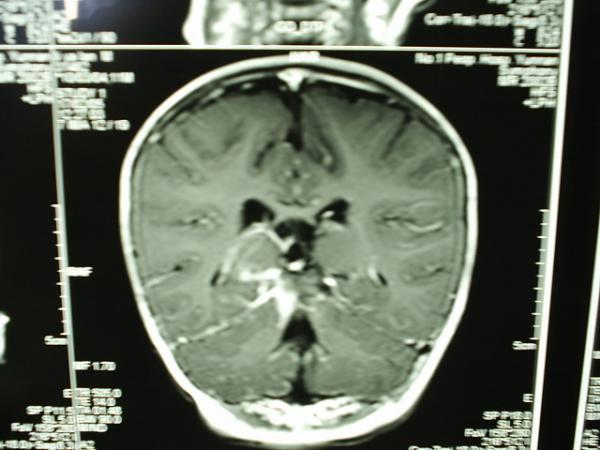

小儿结核性脑膜炎合并脱髓鞘改变MRI

病变部位在右侧大脑半球胼胝体压部强化部分。大家注意看